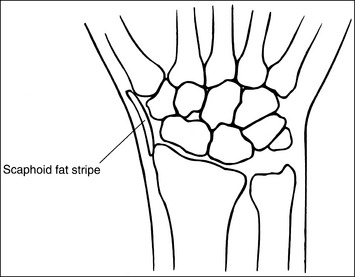

Contrast and density are adequate to demonstrate the scaphoid fat stripe.

• Significance of the scaphoid fat stripe. The scaphoid fat stripe is one of the soft tissue structures that should be visible on all PA wrist projections (Figure 4-30). It is convex and located just lateral to the scaphoid in an uninjured wrist. A change in the convexity of this stripe may indicate to the reviewer the presence of joint effusion or of a radial side fracture of the scaphoid, radial styloid process, or proximal first metacarpal.

• The scaphoid fat stripe is one of the soft tissue structures that should be visible on all PA oblique wrist projections. It is convex and located just lateral to the scaphoid on an uninjured wrist (see Figure 4-30). A change in the shape of this fat stripe or in its proximity to the scaphoid may indicate joint effusion or a radial side fracture.